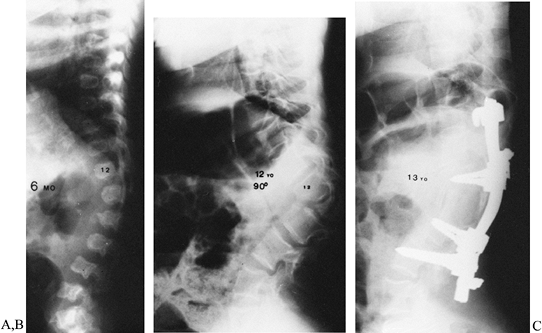

lumbar region (Fig. 158.7). Stabilization and

![]() |

Figure 158.7. A: A 6-month-old girl with achondroplasia, never braced. B: The same patient at age 12 with severe 90° wedging of L-2 with early weakness. C:

One year after anterior decompression and posterior fusion. The patient had an initial postoperative increase in weakness, but recovered fully within 3 months. |